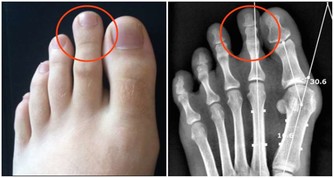

保險起見,他決定找了另一位醫生協助,才發現他腳上的紅色痕跡根本不是血管,是巨大的蠕蟲!

蠕蟲時常會藉由貓狗的排泄物傳染,是一種寄生蟲疾病。

醫生也評斷男子可能是赤腳踩在地板上,才感染到這樣的寄生蟲。

在服用抗寄生蟲的藥物後,這名男子已經完全康復。